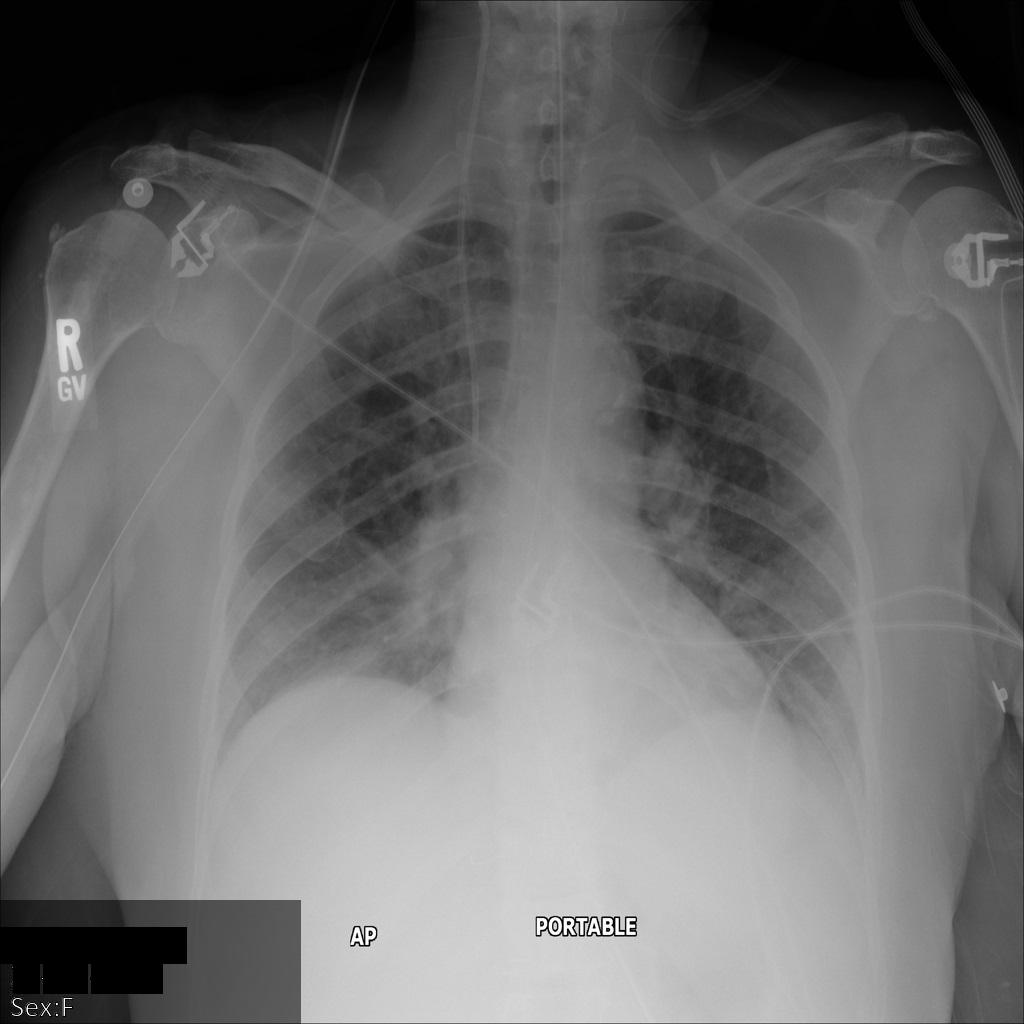

REDACT_SENSITIVE_TEXT 옵션을 사용하여 Cloud Healthcare API에 이미지를 제출하면 이미지가 다음과 같이 표시됩니다.

다음과 같은 상황을 확인할 수 있습니다.

- 이미지 왼쪽 하단의

PERSON_NAME이 수정되었습니다. - 이미지 왼쪽 하단의

DATE이 수정되었습니다.

기본 DICOM infoType에 따라 민감한 텍스트로 간주되지 않으므로 환자 성별이 수정되지 않았습니다.